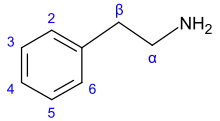

| Alkaloids with nitrogen in the side chain (protoalkaloids) | |||

β-Phenylethylamine derivatives[92]

|

Tyrosine or phenylalanine → dioxyphenilalanine → dopamine → adrenaline and mescaline tyrosine → tyramine phenylalanine → 1-phenylpropane-1,2-dione → cathinone → ephedrine and pseudoephedrine[21][52][142] | Tyramine, ephedrine, pseudoephedrine, mescaline, cathinone, catecholamines (adrenaline, noradrenaline, dopamine)[21][143] | |